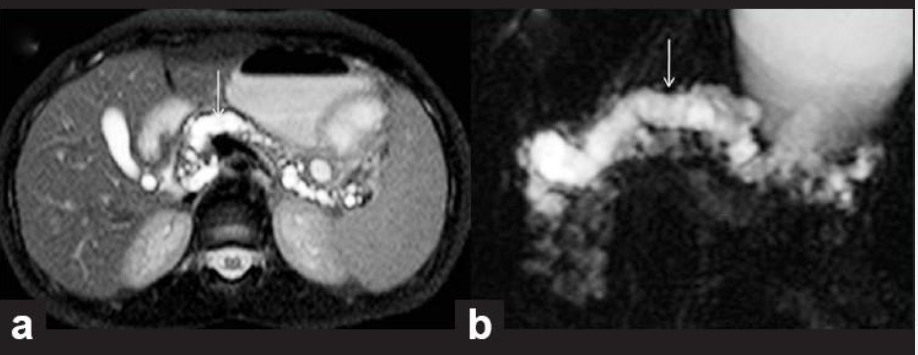

8

Q

מהו הממצא

A